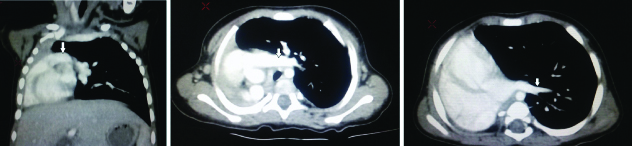

Radiolucency was noted on the medial aspect of right lung field corresponding to left lung herniation. Cardiac shadow could not be recognised on chest X-ray. A provisional diagnosis of right lung whiteout was given. Foreign body entrapment in the main bronchus was suspected with pulmonary aplasia/agenesis as a close differential. Contrast enhanced CT Scan was advised to look for the exact cause which showed absence of right lung tissue with a rudimentary right main bronchus [Table/Fig-2a-c,3a,b]. Right pulmonary artery and vein were also absent. Cardiac apex was on the left side suggesting dextroposition rather than dextrocardia of heart. A final diagnosis of “Right lung aplasia with dextroposition” was given. Symptomatic treatment was given in paediatrics department. Bag and mask ventilation and endotracheal intubation were done for supportive breathing. Patient was observed for eight days in the hospital and then discharged. Patient was being followed-up. She was doing well with occasional low grade fever as seen in the last follow up.

a) Coronal CT image showing absence of right lung tissue with hyperinflated left lung. Left pulmonary artery (arrow); b) Axial CT image showing similar findings as in Table/Fig-2a arrow-left pulmonary artery; c) Axial image showing absence of right lung with hyperinflated left lung herniating to right side and left pulmonary vein (arrow). Right pulmonary artery and vein were absent.